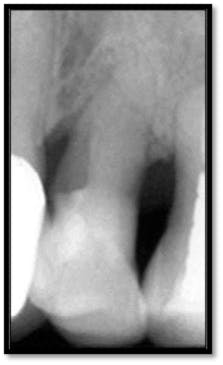

As you can see, the extent of bone loss on the mesial is significant, almost to the apex.14 months post treatment:

MB/ML #12 now probes 3mm (above left), Notice the nice bone fill on the mesial surface (above right)